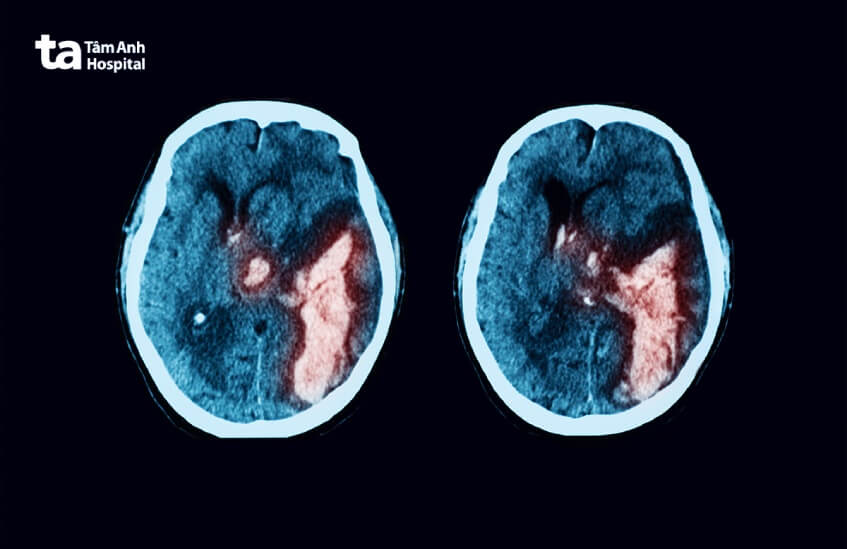

1. Máu tụ nội sọ

Khi sọ não bị chấn thương, vỏ não là bộ phận chịu tổn thương trực tiếp mạnh nhất, kế đến là các khu vực bên trong não. Các động mạch máu não bên trong não khi bị rách, đứt, vỡ sẽ gây ra khối máu tụ nội sọ. Khối máu tụ này có thể xuất hiện tại một nơi hoặc lan tỏa ra nhiều vị trí trong não. (2)

Tùy theo vị trí khối máu tụ nội sọ sẽ có mức độ nguy hiểm và ảnh hưởng đến các loại chức năng thần kinh khác nhau của não, bao gồm: nhận thức, vận động, cảm giác và ngôn ngữ.

Thông thường, khối máu tụ nội sọ sẽ xuất hiện ở dưới hoặc ngoài màng cứng, trong não thất hay tiểu não,… Các khối máu tụ nội sọ có thể gây ra tình trạng gián đoạn lưu thông máu, tăng áp lực nội sọ, máu tràn vào não thất. Hậu quả cũng có thể là xuất huyết não và gây nguy hiểm cho tính mạng người bệnh.